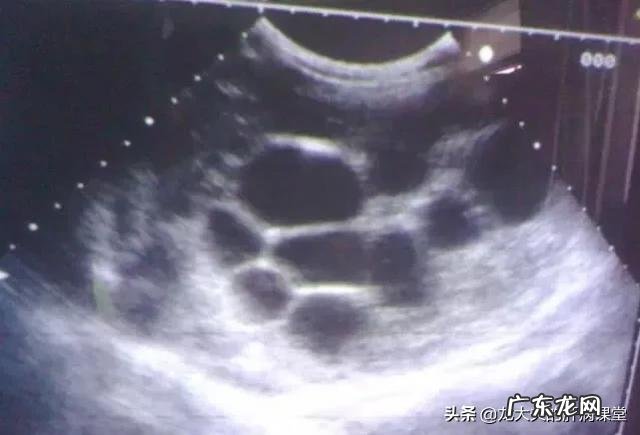

我们可以想象它是一个水泡 , 当水泡的出口和入口都封闭的时候 , 水泡里面的水出不去 , 水泡的壁越来越厚 。在B超或者CT上看到的囊肿 , 就是这个样子 , 囊肿里面由于是液体 , 密度会比周围的脏器要低一些 。

还有一种肝囊肿 , 是先天性多囊性肝病 , 这是一种遗传性的疾病 , 先天就有的 。这种囊肿不单见于肝脏 , 有一半的人同时还伴有肾囊肿 , 有一些患者就能见到这样的情况 。